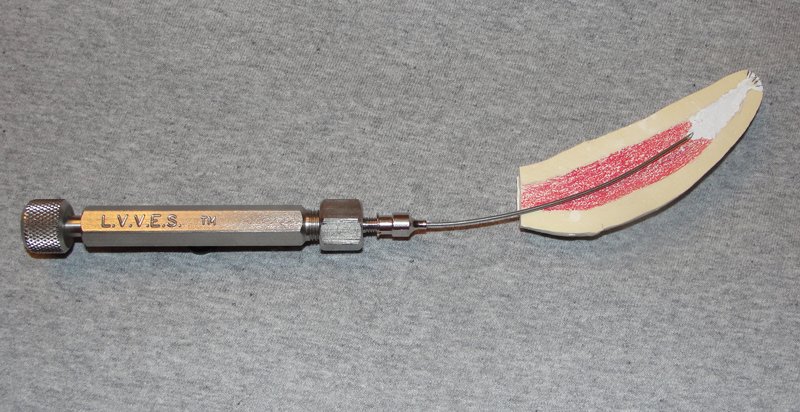

Prior to treating a specific animal, the operator must review the anatomy to be encountered. Today this is much easier with many resources on the internet. However, physical specimens of skulls with intact dentitions are the best aid. Over my tenure at MCZ we have developed relationships with regional museums to acquire such specimens. Designated animals from our collection that die are prepared into reference specimens for us to keep or have accessible.

Paleontological reference texts are among the best dental formulae and anatomical resources. Because teeth are the longest surviving physical remains of a mammal, paleontologists have studied and documented them exquisitely. However, they don't reference teeth root anatomy which is so critical to dental treatment.

The developmental and functional physiology of dentitions is also very important information in consideration of treatment. These will require researching various sources including natural history reference texts and the academic literature. In recent years detailed information of this type for equidae has become available, driven by the developing veterinary specialty of equine dentistry.

An example of utilizing a skull specimen for treatment planning is to become familiar with accessing the apex of a canine when an apisectomy/retrograde fill endodontic procedure is appropriate.